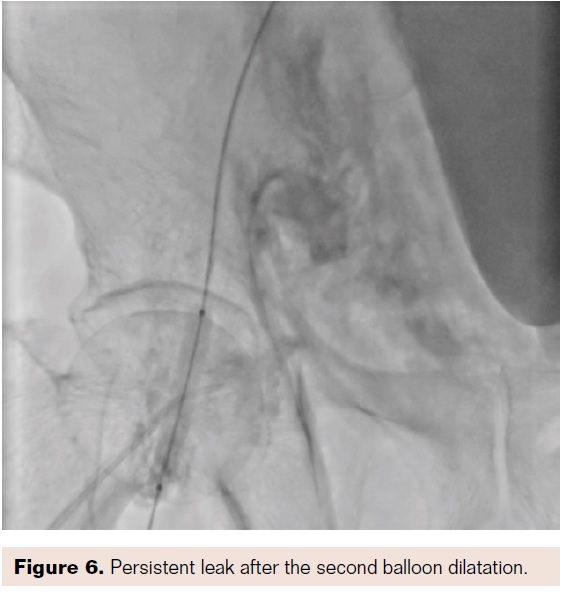

There was a small leakage seen after this from the right SFA (Figure 6). On waiting further, no further dye leakage was seen on the last check shot (Figure 7). The patient remained stable hemodynamically, and a follow-up ultrasound was performed. This showed a small hematoma in the right femoral area of 5 x 5 cm. However, the patient improved and was discharged after a course of antibiotics (total hospital stay after the procedure was 9 days).